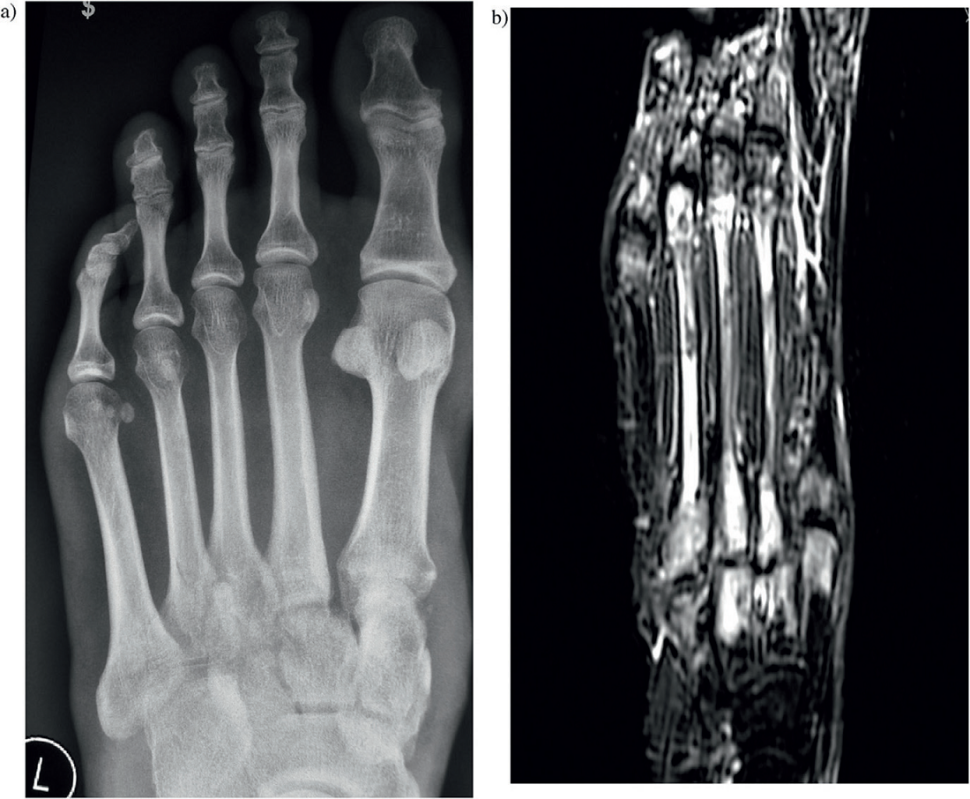

Złamanie stawu Lisfranca z bocznym zwichnięciem drugiej kości śródstopia w stosunku do kości klinowatej pośredniej i rezonans magnetyczny uszkodzonej stopy pokazujący stłuczenie wszystkich okolicznych kości

Ryc. 6a. Złamanie stawu Lisfranca z bocznym zwichnięciem drugiej kości śródstopia w stosunku do kości klinowatej pośredniej (3 mm). b. Rezonans magnetyczny uszkodzonej stopy pokazujący stłuczenie (bone bruise) wszystkich okolicznych kości.